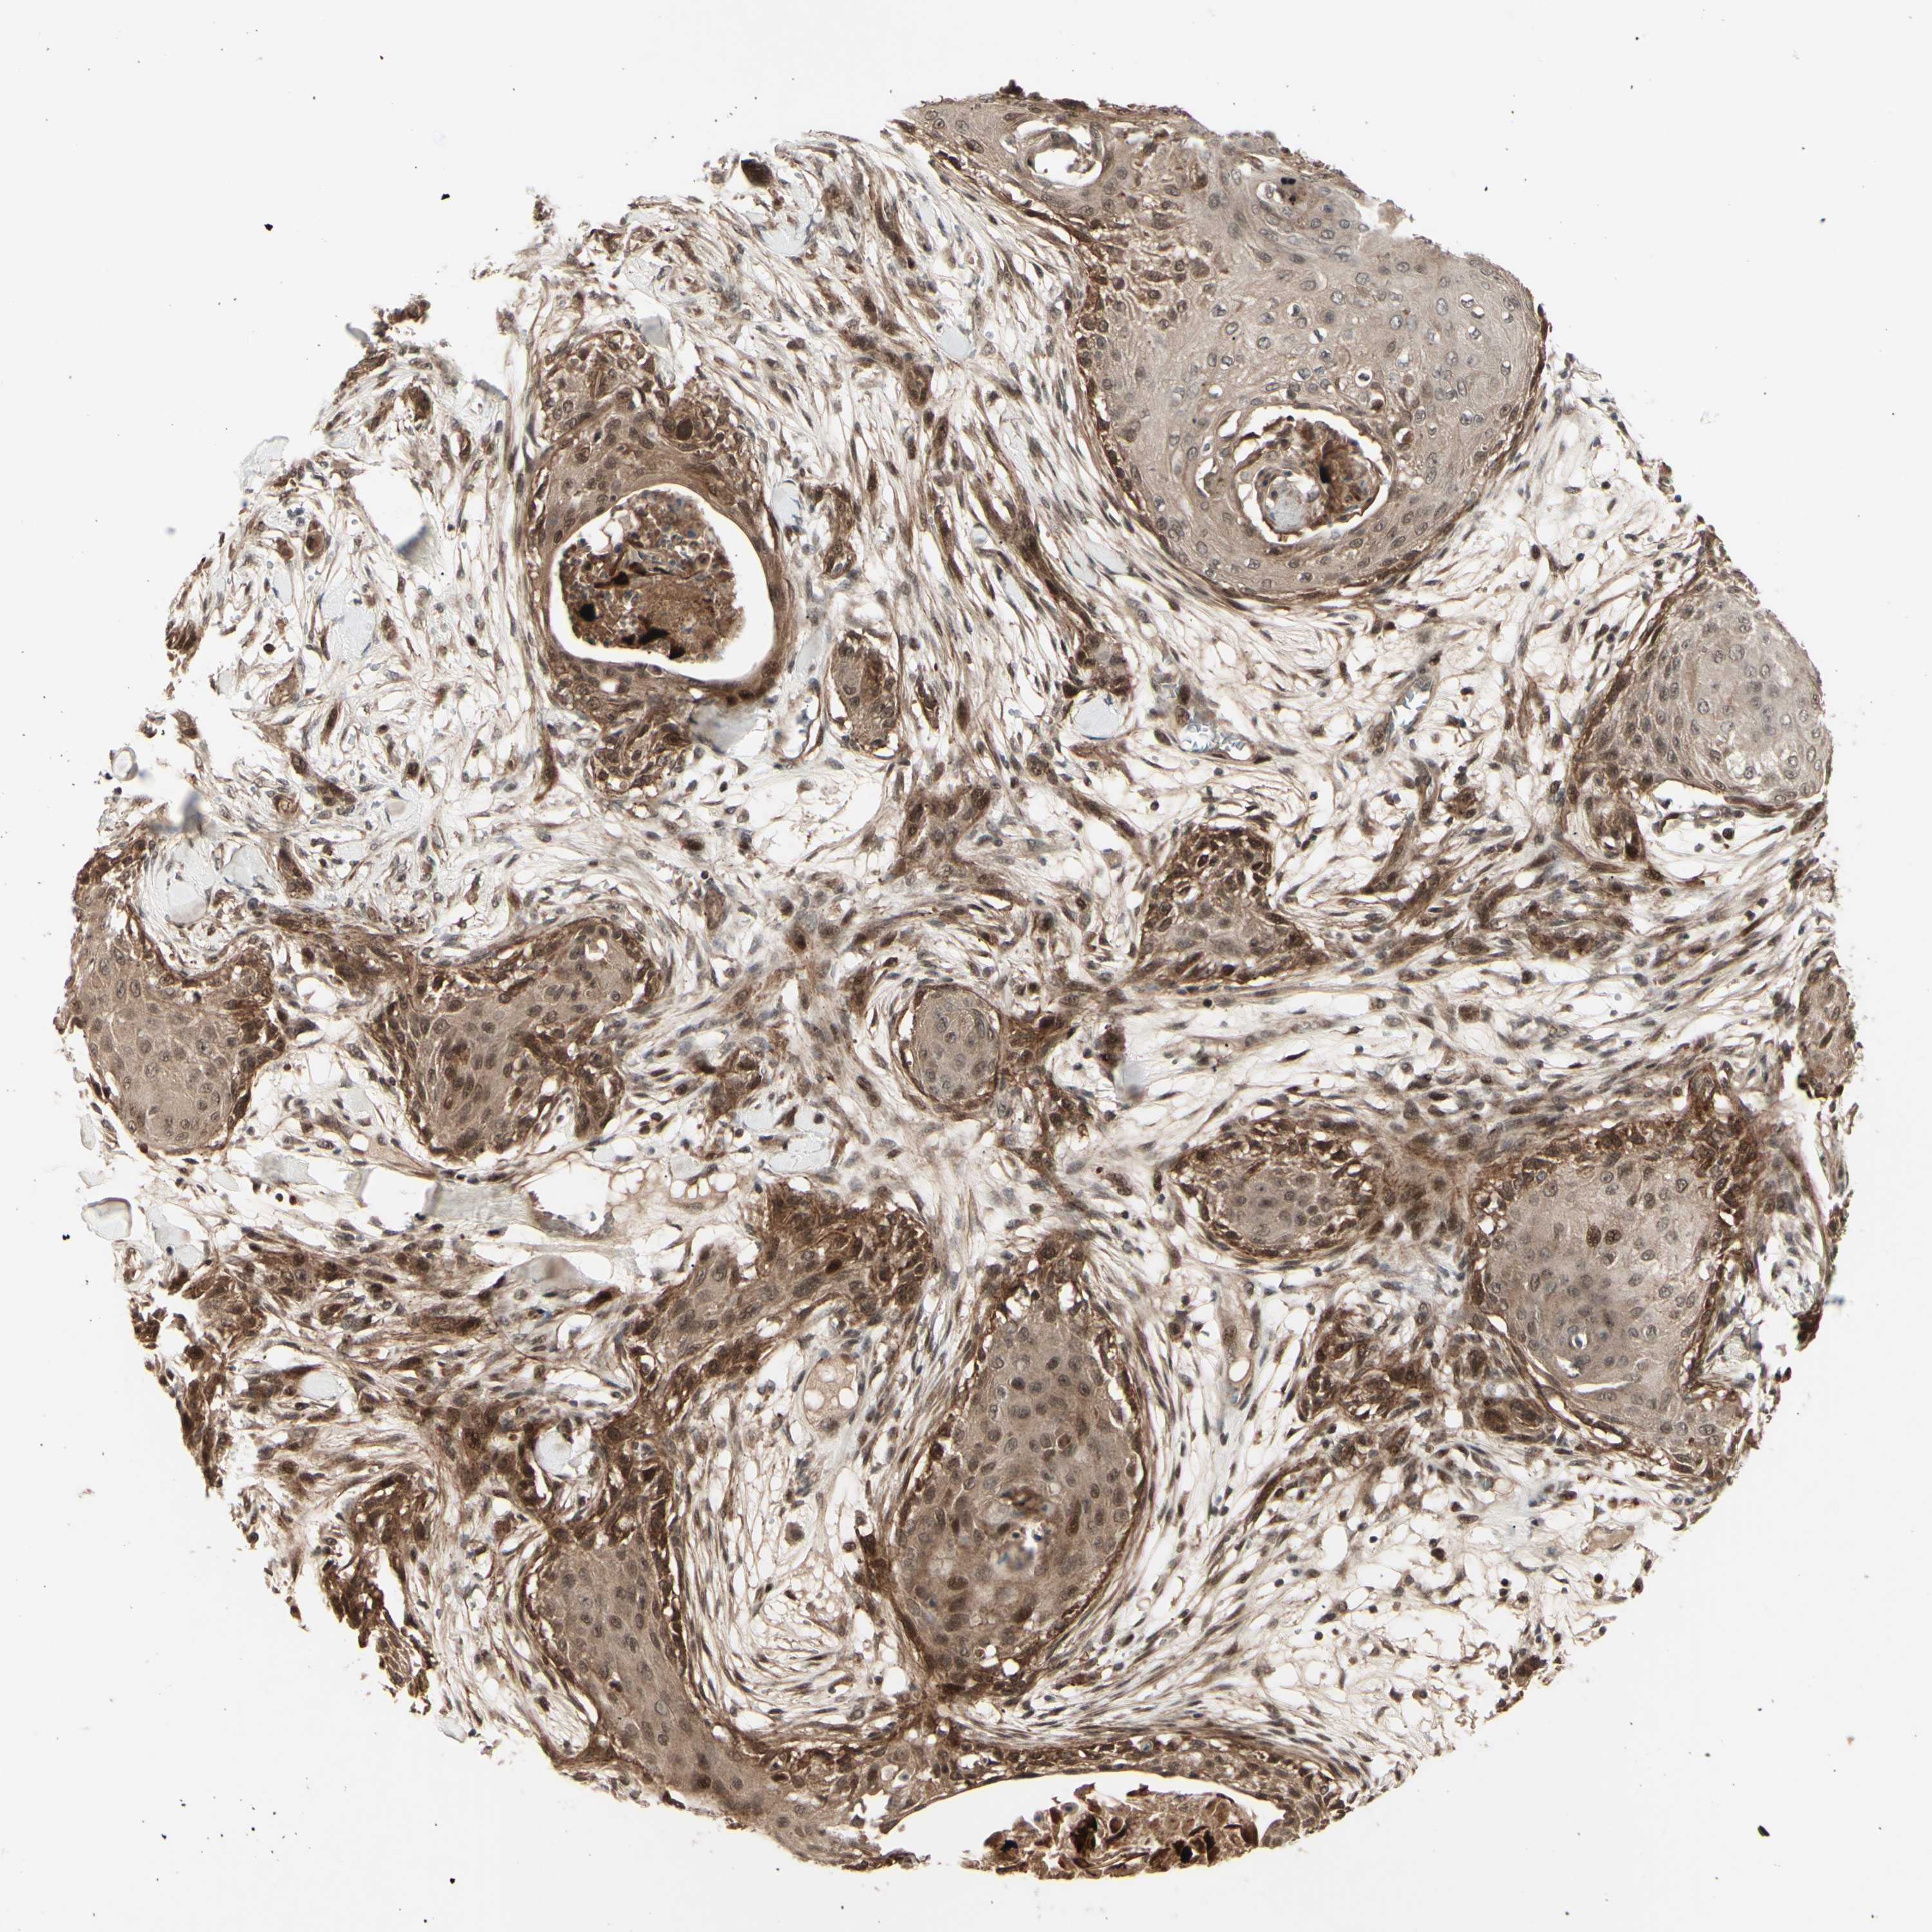

SKIN CANCER - Protein expressioni

A mouse-over function shows sample information and annotation data. Click on an image to view it in a full screen mode. Samples can be filtered based on level of antibody staining by selecting one or several of the following categories: high, medium, low and not detected. The assay and annotation is described here.

Antibody stainingi

Antibody staining in the annotated cell types in the current human tissue is reported as not detected, low, medium, or high, based on conventional immunohistochemistry profiling in selected tissues. This score is based on the combination of the staining intensity and fraction of stained cells.

Each image is clickable and will lead to virtual microscopy that enables deeper exploration of all samples and also displays staining intensity scores, fraction scores and subcellular localization as well as patient and tissue information for each sample.

Antibody HPA010859

Staining

High

Intensity

Quantity

Location

Basal cell carcinoma